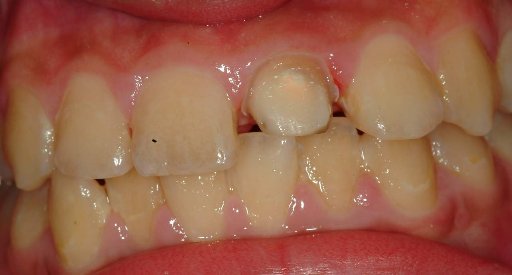

根管內稍做修形放入玻璃纖維 , 修形成全瓷冠需要的牙齒形狀,以雙線排齦方式印模(見圖四) , 並以數位照相及比色機比色(圖五)

圖四 |